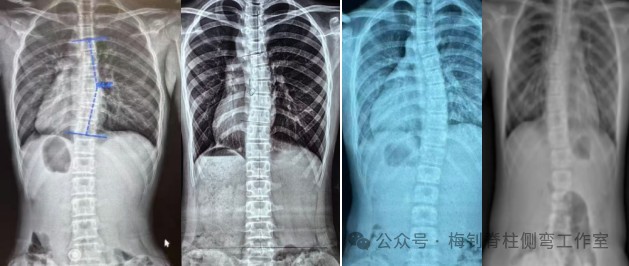

脊柱侧弯的危害

脊柱侧弯首先影响人体外观,进而可能对患儿心理造成影响;侧弯大于30度,后期可能会出现腰背疼痛;重度脊柱侧弯可导致胸腔变形,致心肺功能受损(如心跳加速、限制性通气功能障碍等)